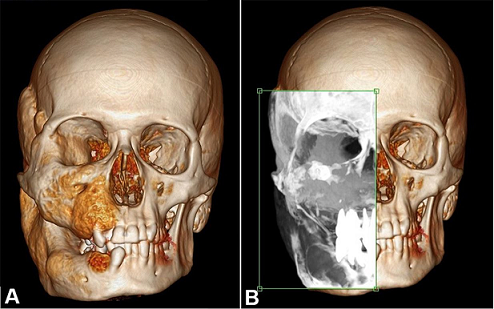

Neither patient exhibited trauma and/or associated infections, and both had normal laboratory test findings. The facial CT images of patient 1 showed an expansive lesion with the ground glass appearance that involved the skull base and the right maxillary, zygomatic, sphenoidal, temporal, frontal, and mandibular bones ( Figure 3).

Involvement of the orbital bone resulted in a decrease in the socket volume and optic canal diameter, which explained the exophthalmia and vision loss. Bone scintigraphy showed osteogenic activity in the right craniofacial region, without involvement of other skeletal structures. The clinical features and laboratory and radiographic findings confirmed the diagnosis of MFD. The patient underwent osteoplasty of the affected maxillary, zygomatic, mandibular, and temporal bones for the restoration of facial harmony. The surgery was preceded by virtual planning ( Figure 4).